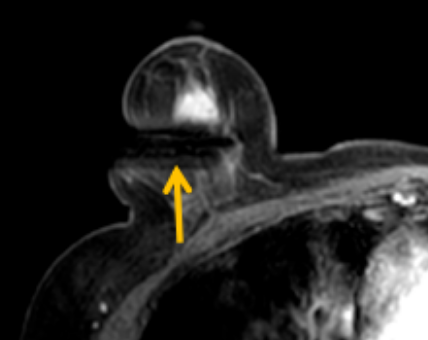

陳寶瑩評(píng)估圖像后發(fā)現(xiàn)病變?yōu)閮H僅在磁共振增強(qiáng)時(shí)顯示,為非腫塊樣病變,比較散,必須取得足夠多的組織才能確保病理檢查的準(zhǔn)確性,常用的核芯針活檢獲取的組織較少,因此最終確定了磁共振引導(dǎo)下行真空輔助抽吸旋切活檢。取得患者及家屬認(rèn)可后,陳寶瑩帶領(lǐng)團(tuán)隊(duì)開始進(jìn)行術(shù)前準(zhǔn)備。

針對(duì)患者乳房小固定難度大這一問題,陳寶瑩通過巧妙體位和固定器的調(diào)整,順利固定好乳房。經(jīng)過磁共振多模態(tài)掃描,陳寶瑩找出病變活性成分相對(duì)集中區(qū)域,精準(zhǔn)確定穿刺路徑,置入引導(dǎo)針、旋切針,到位后多角度旋切取出足量組織,拔除旋切針后即時(shí)行磁共振掃描,精準(zhǔn)取得組織且術(shù)區(qū)出血很少,遂加壓包扎,整個(gè)過程非常順利,旋切活檢后患者回家休息。兩天后隨訪,李女士沒有任何不適,五天后皮膚上幾毫米的小切口已經(jīng)愈合。最終病理結(jié)果證實(shí)為乳腺導(dǎo)管原位癌,為早期乳腺癌,為患者后續(xù)針對(duì)性治療奠定了基礎(chǔ)。